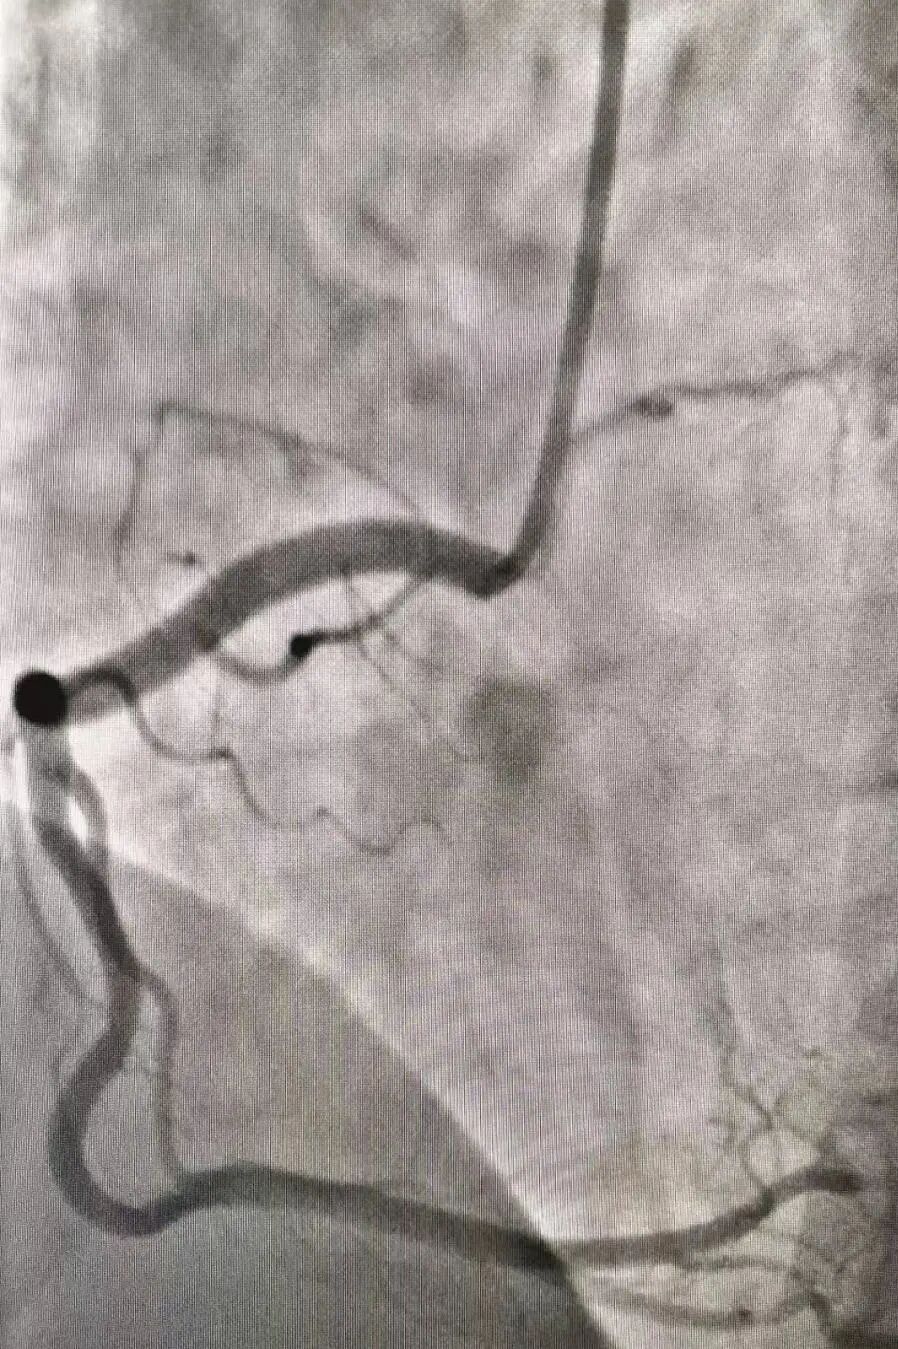

腹部血管系统

DSA 技术用于显示如下部位:腹主动脉,肾动脉,腹腔动脉,肠系膜上动脉,肠系膜上静脉,腹动脉狭窄,动脉粥样硬化。该技术目前广泛应用于临床的肝肾等重要动脉造影。